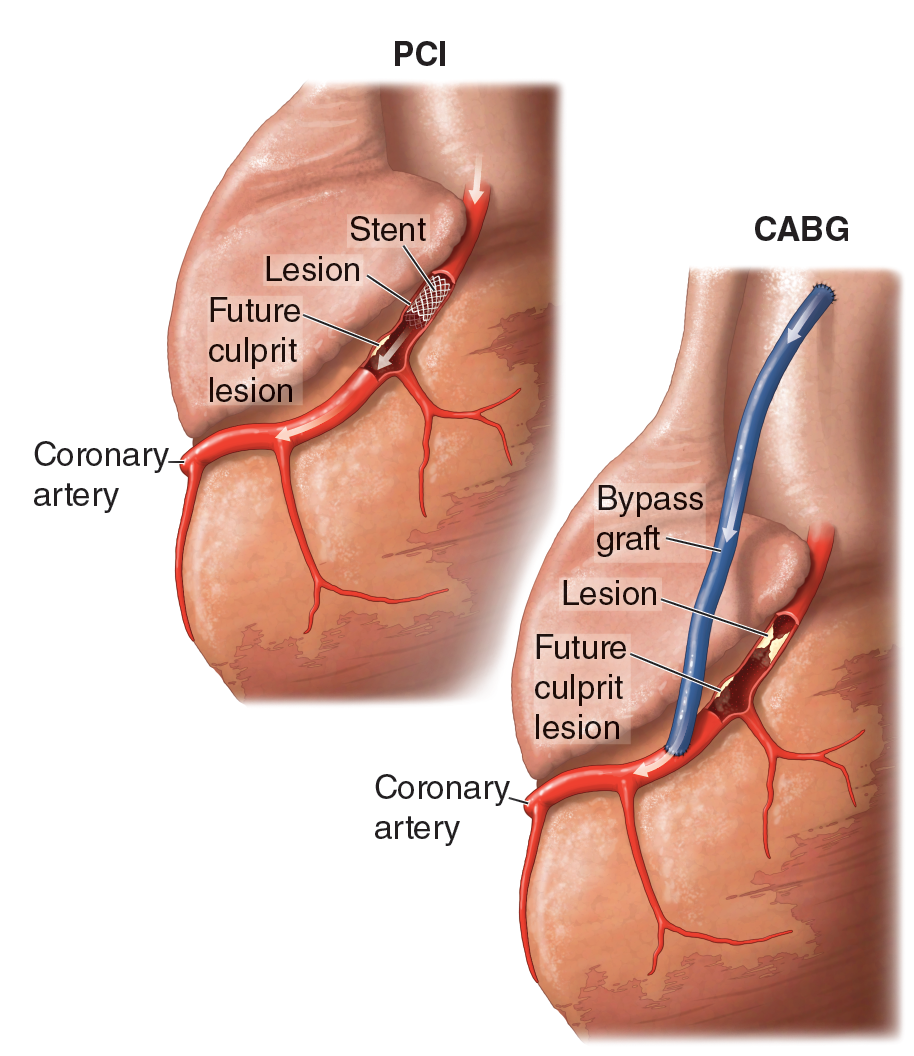

Medical Illustration

All images are works made for hire and are the exclusive property of the client. These are shown as sample purposes of my work only. For licensable work, please see my Illustration Services page.

Medical Illustrator for Precision Graphics, Lachina, and Human Kinetics Publishing (current)

Contract freelancer for many others, some examples of my work below.